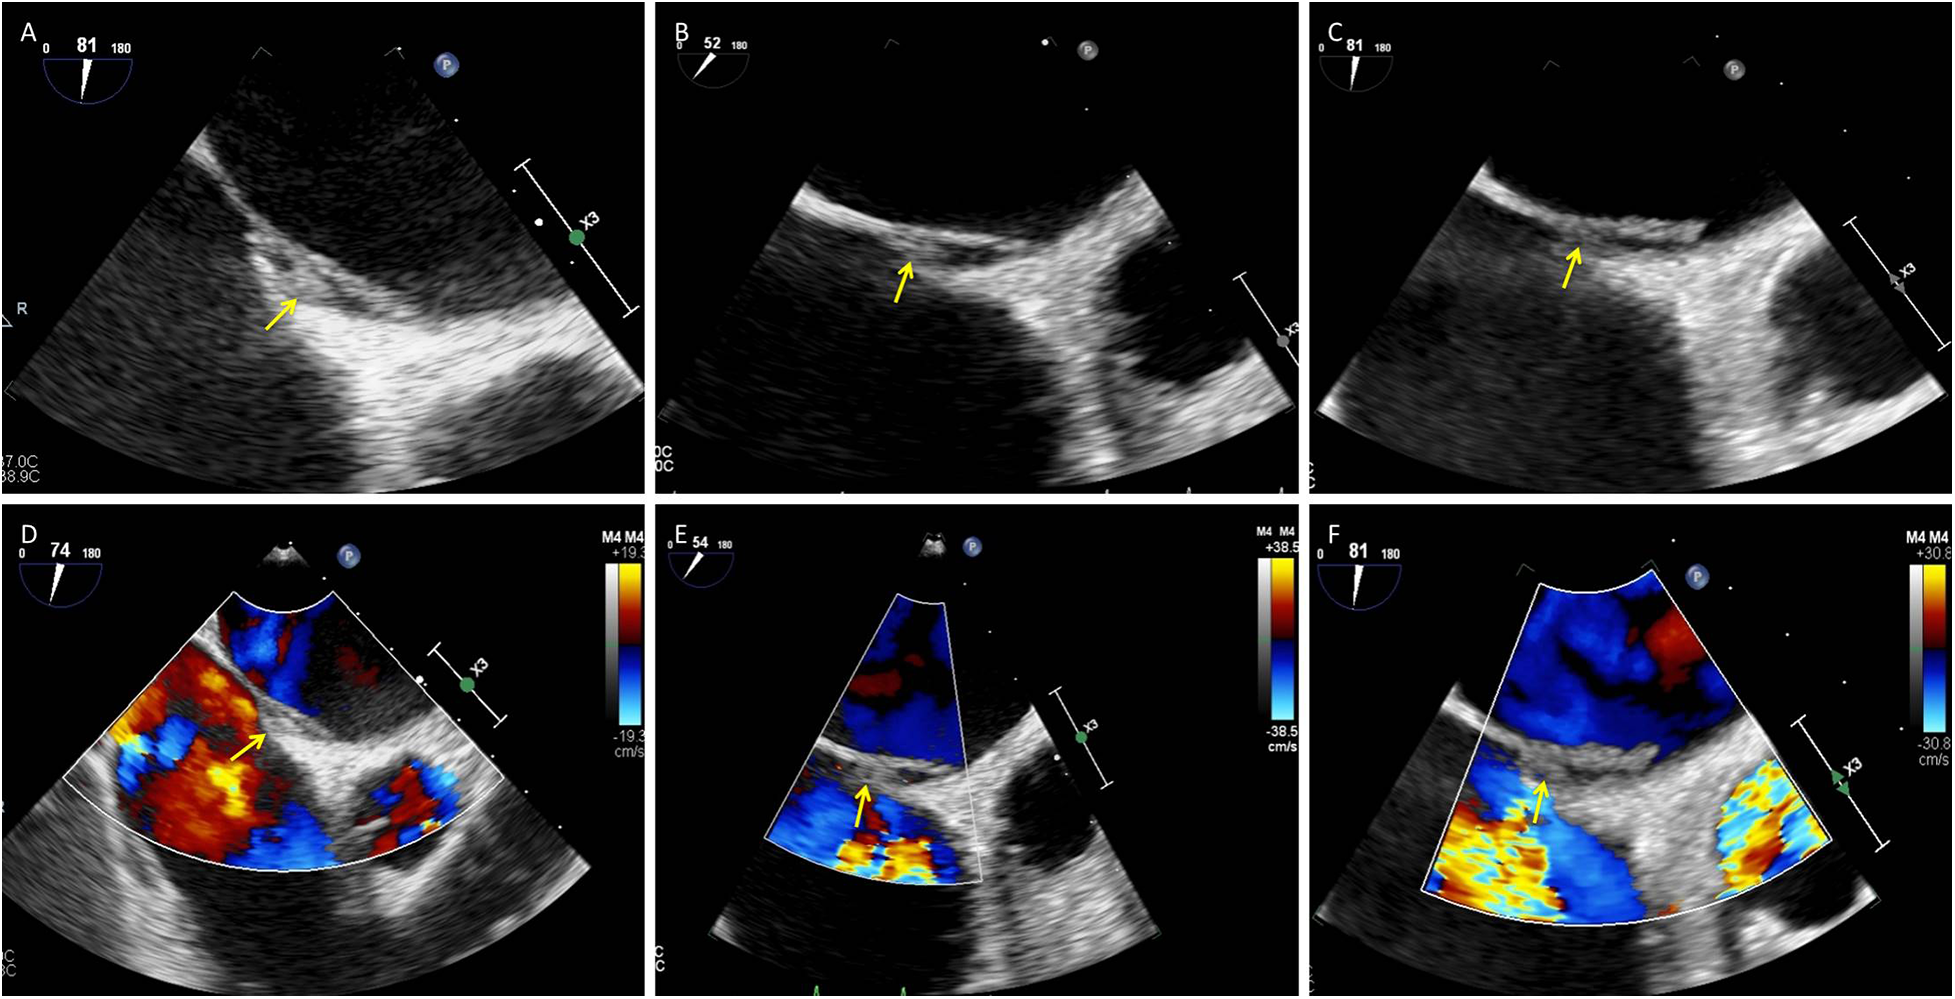

A 75-year-old woman was admitted with a chief complaint of recurrent chest tightness for more than 3 years, which had worsened over the two days prior to admission, accompanied by shortness of breath and dizziness. Her medical history included hypertension for more than 20 years and diabetes for more than 2 years. Laboratory findings included an N-terminal pro–B-type natriuretic peptide (NT-proBNP) concentration of 1,605 ng/L (0–125), a hypersensitive troponin concentration of 0.014 µg/L, a D-dimer concentration of 0.51 mg/L FEU (0–0.5), and an electrocardiogram demonstrating persistent atrial fibrillation (AF) with ST–T abnormalities. Cranial magnetic resonance imaging (MRI) revealed small chronic ischemic infarcts in the right corona radiata and bilateral centrum semiovale, with no evidence of acute infarction. TTE revealed biatrial enlargement, mild mitral regurgitation, moderate tricuspid regurgitation, borderline pulmonary hypertension, and normal left ventricular systolic function. Transesophageal echocardiography (TEE) was performed to exclude intracardiac thrombus prior to planned radiofrequency catheter ablation; importantly, no thrombus was detected in either the left atrial appendage or the right atrial appendage. Initially, TEE revealed separation of the primary and secondary septum, with a fixed, slender, medium-echo thrombus measuring approximately 3.1 × 9.1 mm straddling the PFO (Figures 2A,D). Spontaneous echocardiographic contrast in both atria suggested blood stasis. Anticoagulation therapy with 20 mg rivaroxaban once daily was immediately initiated. TEE performed 54 days later revealed a thrombus measuring approximately 2.3 × 5.6 mm (Figures 2B,E). Final TEE performed 141 days later revealed a thrombus measuring 2.1 × 4.6 mm (Figures 2C,F); moreover, no peripheral embolic events occurred during the treatment period. The thrombus decreased in size following oral anticoagulation treatment with rivaroxaban.

Figure 2

Small presumed in situ thrombus within the PFO tunnel with interval regression under oral anticoagulation: serial TEE. (A–C) Grayscale TEE images (mid-esophageal views) obtained at baseline, day 54, and day 141 show a small, relatively fixed thrombus within the PFO tunnel (arrows). The thrombus measured 3.1 × 9.1 mm at baseline (A), 2.3 × 5.6 mm on day 54 (B), and 2.1 × 4.6 mm on day 141 (C). (D–F) Corresponding color Doppler images at the same time points depict interatrial flow across the PFO (arrows). PFO, patent foramen ovale; TEE, transesophageal echocardiography; RA, right atrium; LA, left atrium.

In contrast, in situ thrombi are generally smaller, less mobile, and more closely adherent to the interatrial septum or PFO tunnel. They tend to occur in patients with underlying cardiac disease or atrial factors such as AF or structural abnormalities and may lack an obvious peripheral venous source (6, 11). In Case 2, a 75-year-old woman with hypertension and persistent AF had biatrial enlargement and spontaneous echocardiographic contrast, indicating pronounced atrial blood stasis. TEE revealed separation of the primary and secondary septa and a small, relatively fixed, slender thrombus within the PFO tunnel that gradually regressed under oral anticoagulation, without clinical evidence of pulmonary embolism or peripheral embolic events during 141 days of follow-up. These observations are more compatible with in situ thrombus formation within the PFO tunnel than with a large embolus in transit.

Nevertheless, the diagnostic work-up in Case 2 was incomplete: lower-extremity venous Doppler ultrasound, contrast-enhanced TTE/TEE with bubble study, and formal thrombophilia testing were not performed, and AF itself is a major confounder of cardioembolism. A venous source and paradoxical embolism, therefore, cannot be definitively excluded, and our classification of this lesion as most compatible with in situ PFO thrombus should be regarded as presumptive rather than conclusive. From a practical standpoint, signs of acute pulmonary embolism, lower extremity DVT, right ventricular pressure overload, and a large, highly mobile serpiginous thrombus spanning both atria favor an embolus in transit. Conversely, small, relatively fixed thrombi confined to the PFO tunnel in patients with AF or other prothrombotic cardiac conditions, in the absence of clear peripheral venous triggers, are more suggestive of in situ formation—but as illustrated by Case 2, such distinctions are sometimes probabilistic rather than definitive.